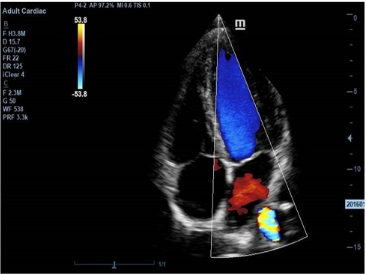

· 智能斑点噪声抑制成像iClear

智能图像优化处理技术,有效抑制二维图像的斑点噪声,增强图像对比分辨率,

使 组织边界显示更清晰、回声更细腻。